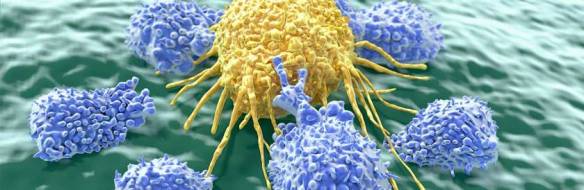

The people with hidden immunity against Covid-19. T cells (T lymphocytes) are a source of immunity to Covid-19. … the first line of defence is the innate immune system, which involves white blood cells and chemical …

When researchers tested blood samples taken years before the pandemic started, they found long lasting T immune cells which were specifically tailored to detect proteins on the surface of Covid-19.

40-60% of unexposed individuals have T cells, which give them Innate natural Immunity to Covid 19. (Note: this means you’re unlikely to get Covid and if you did it would be mild.. you still might get it).

The people with hidden immunity against Covid-19. T cells (T lymphocytes) are a source of immunityto Covid-19. … the first line of defence is the innate immune system, which involves white blood cells and chemical …

When researchers tested blood samples taken years before the pandemic started, they found long lasting T immune cells which were specifically tailored to detect proteins on the surface of Covid-19.

40-60% of unexposed individuals have T cells, which give them Innate natural Immunity to Covid 19. (Note: this means you’re unlikely to get Covid and if you did it would be mild.. you still might get it).

Suggests that T cell immunity triggered by earlier exposure to other corona viruses (common cold) protects against Covid.